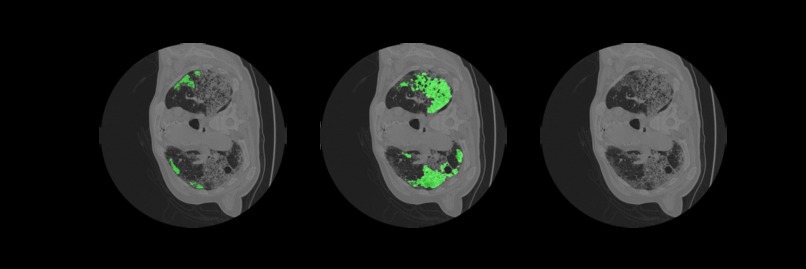

The following is an AI medical segmentation tool for detecting ground-glass, consolidation and pleural effusion in patient lung CT scans. Some reports have shown that ground-glass/consolidation measurements can further enhance the prognosis estimation for Covid-19 patients.